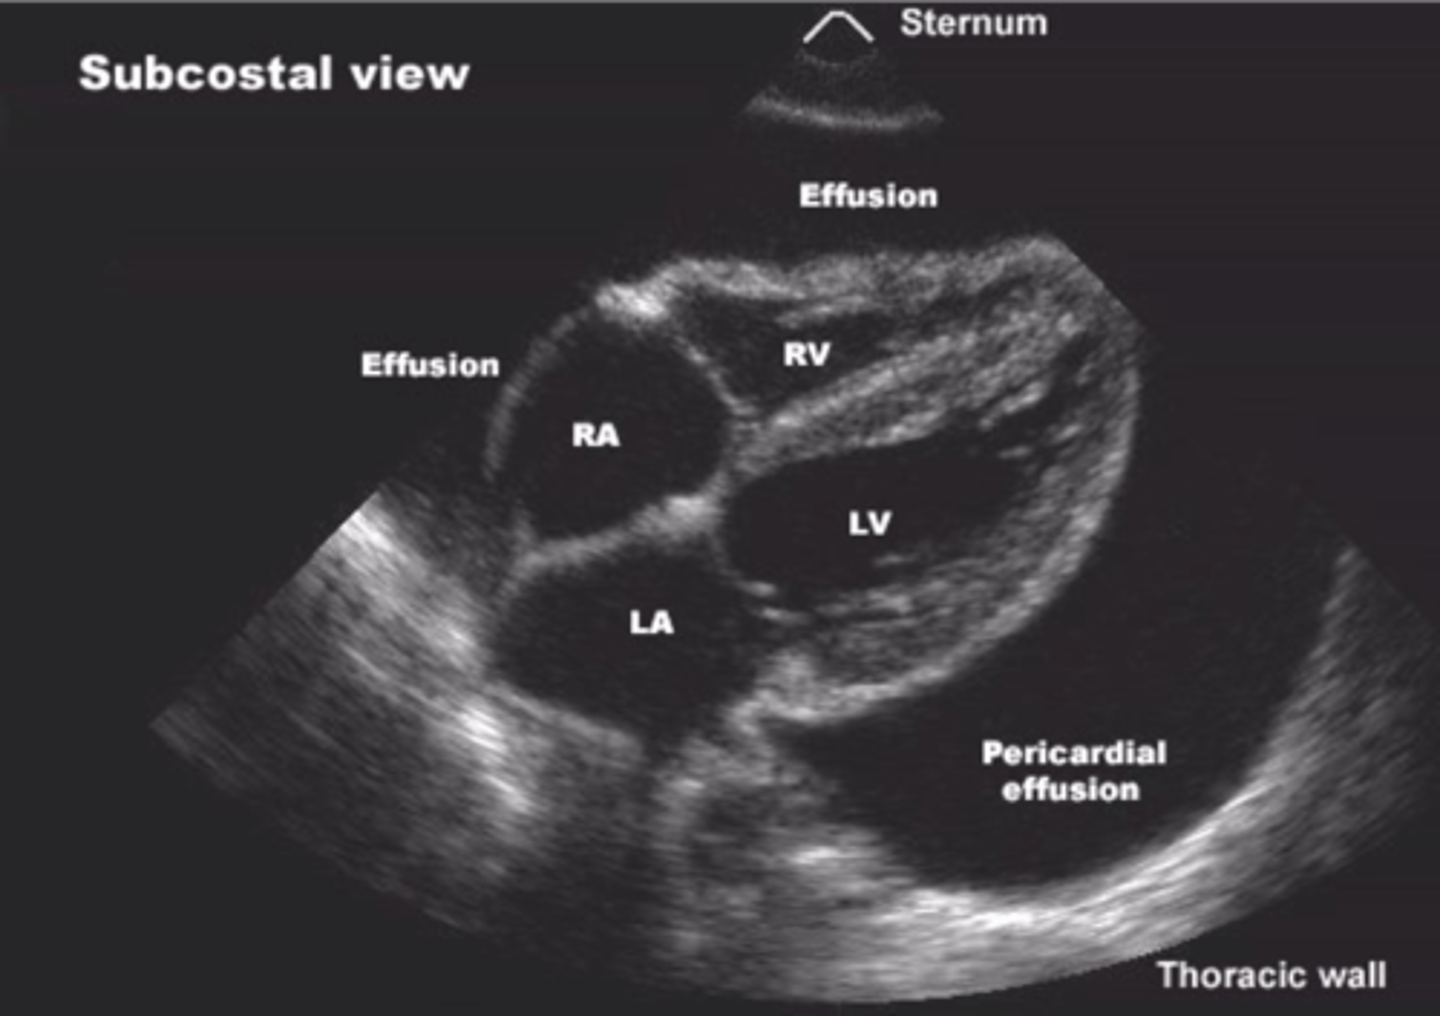

pericardium

echocardiogram

ultrasound of the heart